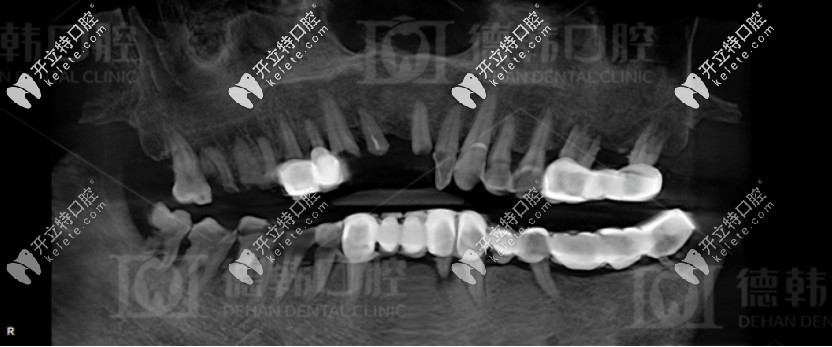

拔牙前爺爺?shù)恼掌?/strong>

沒(méi)有意識(shí)到牙齒缺失不修復(fù)的危害

據(jù)爺爺講述:他剛開始跟多數(shù)人一樣,覺(jué)得缺牙沒(méi)啥大不了的,但是后來(lái)在牙齒陸陸續(xù)續(xù)都開始松動(dòng)掉落時(shí),才意識(shí)到問(wèn)題的重要性。

德韓口腔先是對(duì)他進(jìn)行了全面的口腔檢查,發(fā)現(xiàn)其患有重度的牙周病,而且爺爺全口牙齒松動(dòng),牙列缺損,上下頜骨重度萎縮,無(wú)法保留口腔里的余牙,只能全部拔掉。

種植前爺爺?shù)难榔?/strong>